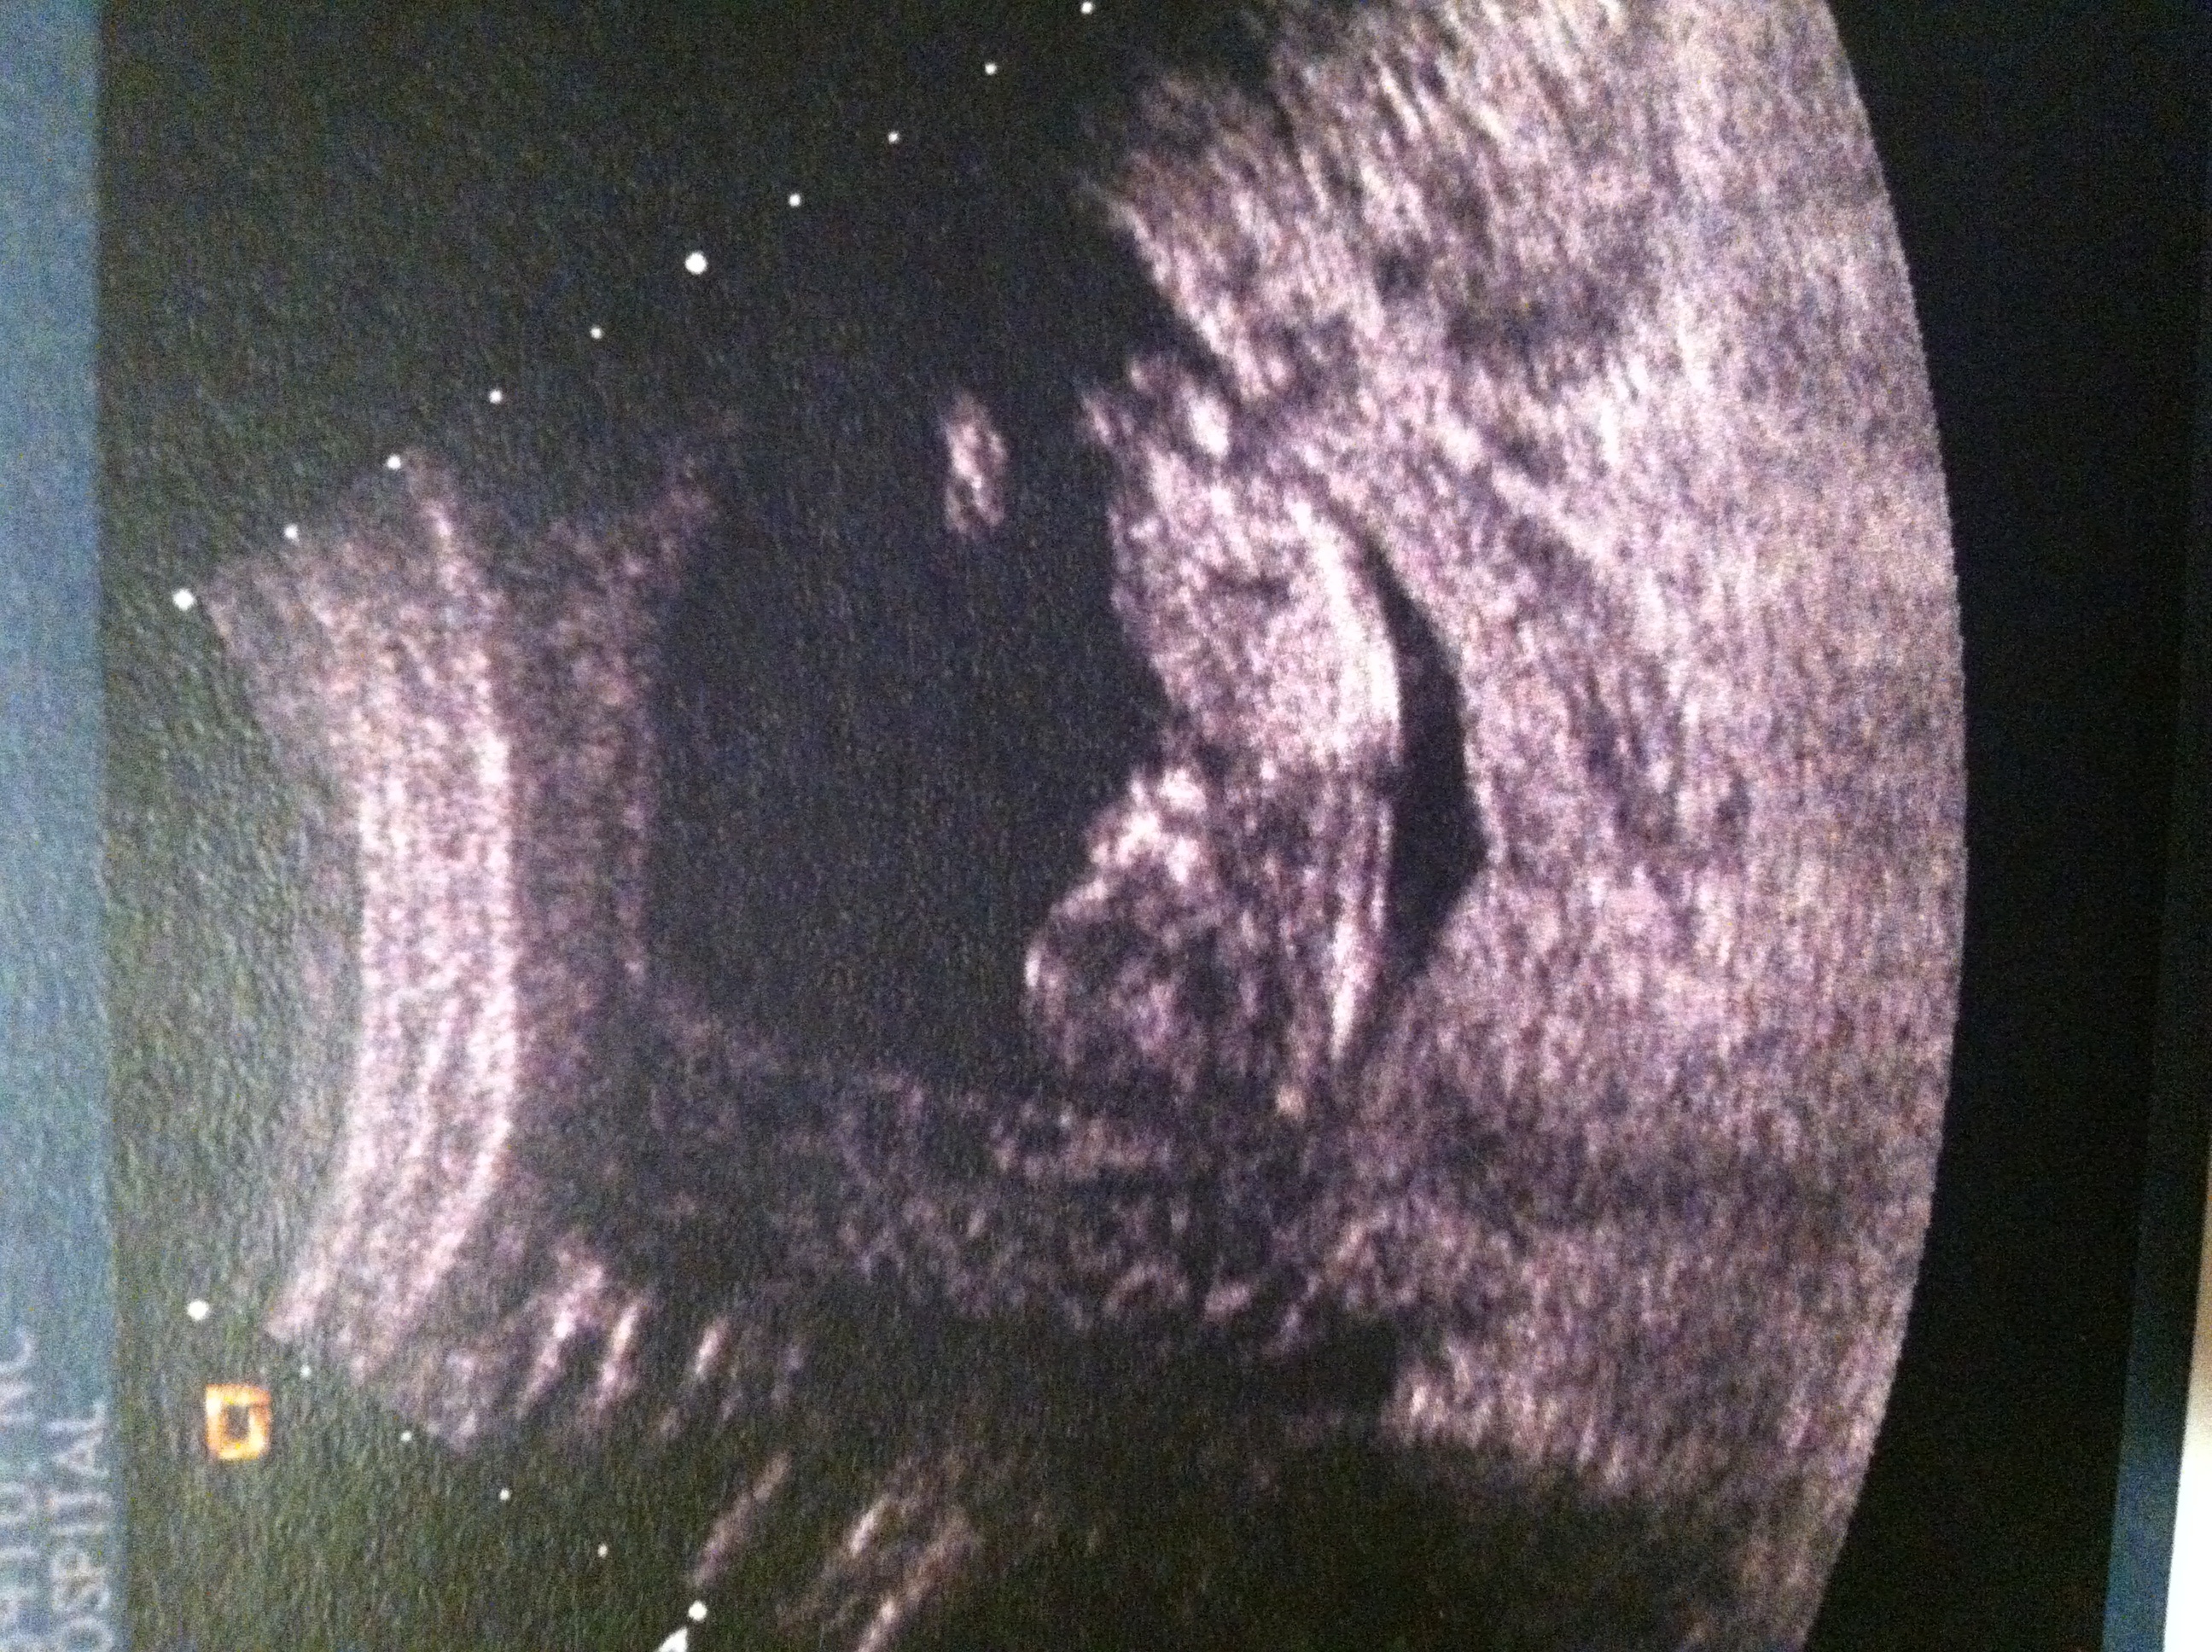

This is at 13.1 weeks, although baby was measuring a bit big- so maybe 13.4

Technician said she is leaning girl, but please what do you think?